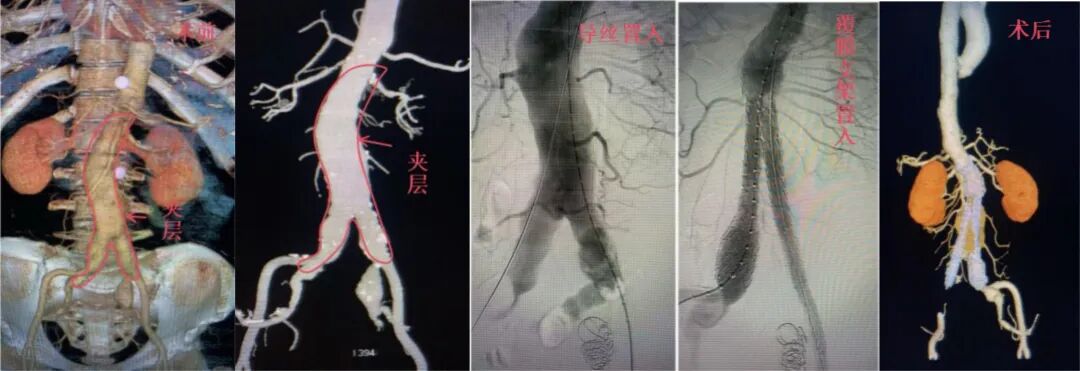

男性,74岁,有10年糖尿病史,确诊腹主动脉瘤累及双侧髂动脉,合并多支内脏血管狭窄及肾动脉小夹层。团队顺利实施腹主动脉分支覆膜支架置入术,术后血管通畅,患者恢复良好。